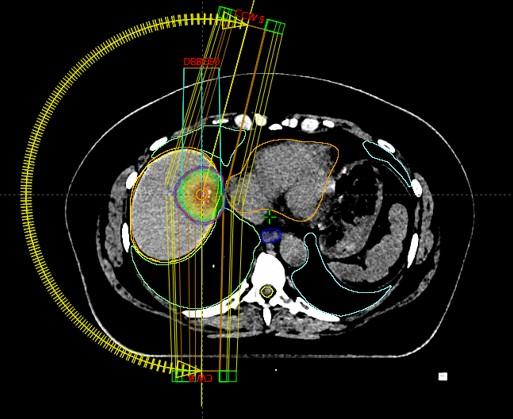

Pluća